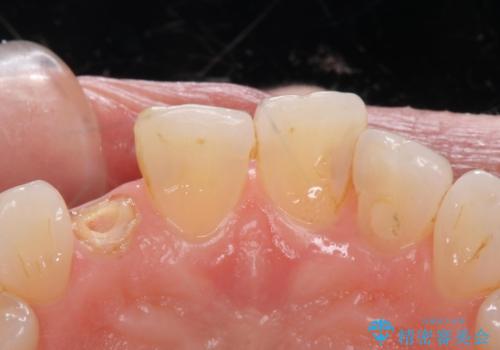

- 右上の前歯が取れたとのことで来院された患者様です。

再根管治療からのやり直しをご提案しましたが、ご希望されなかったため土台(コア)のやりかえからとなりました。

- 右上2 仮歯/11,000円 ファイバーコア/22,000円 ジルコニアクラウン(スペシャル)/154,000円 合計187,000円費用は治療当時の料金となります